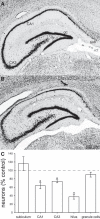

Previous studies suggest that spontaneous seizures in patients with temporal lobe epilepsy might be preceded by increased action potential firing of hippocampal neurons. Preictal activity is potentially important because it might provide new opportunities for predicting when a seizure is about to occur and insight into how spontaneous seizures are generated. We evaluated local field potentials and unit activity of single, putative excitatory neurons in the subiculum, CA1, CA3, and dentate gyrus of the dorsal hippocampus in epileptic pilocarpine-treated rats as they experienced spontaneous seizures. Average action potential firing rates of neurons in the subiculum, CA1, and dentate gyrus, but not CA3, increased significantly and progressively beginning 2-4 min before locally recorded spontaneous seizures. In the subiculum, CA1, and dentate gyrus, but not CA3, 41-57% of neurons displayed increased preictal activity with significant consistency across multiple seizures. Much of the increased preictal firing of neurons in the subiculum and CA1 correlated with preictal theta activity, whereas preictal firing of neurons in the dentate gyrus was independent of theta. In addition, some CA1 and dentate gyrus neurons displayed reduced firing rates preictally. These results reveal that different hippocampal subregions exhibit differences in the extent and potential underlying mechanisms of preictal activity. The finding of robust and significantly consistent preictal activity of subicular, CA1, and dentate neurons in the dorsal hippocampus, despite the likelihood that many seizures initiated in other brain regions, suggests the existence of a broader neuronal network whose activity changes minutes before spontaneous seizures initiate.